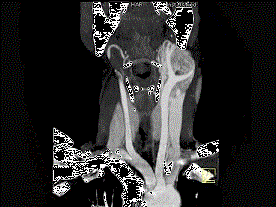

问题 女,39岁,左颈部可扪及一肿块,无发热,无疼痛,CT如图所示,最可能的诊断是 ( )

选项 A、颈部海绵状血管瘤 B、颈动脉瘤 C、颈动脉体瘤 D、颈部神经纤维瘤 E、颈部神经鞘瘤

答案 C